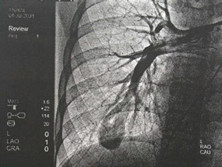

先天性肺动静脉瘘

(又名Rendu-Osl、动静脉瘤、动静脉瘘、动静脉血管瘤)

先天性肺动-静脉瘘(PAVF)又称动静脉瘤,是一种常见的先天性发育畸形,胚胎期肺...